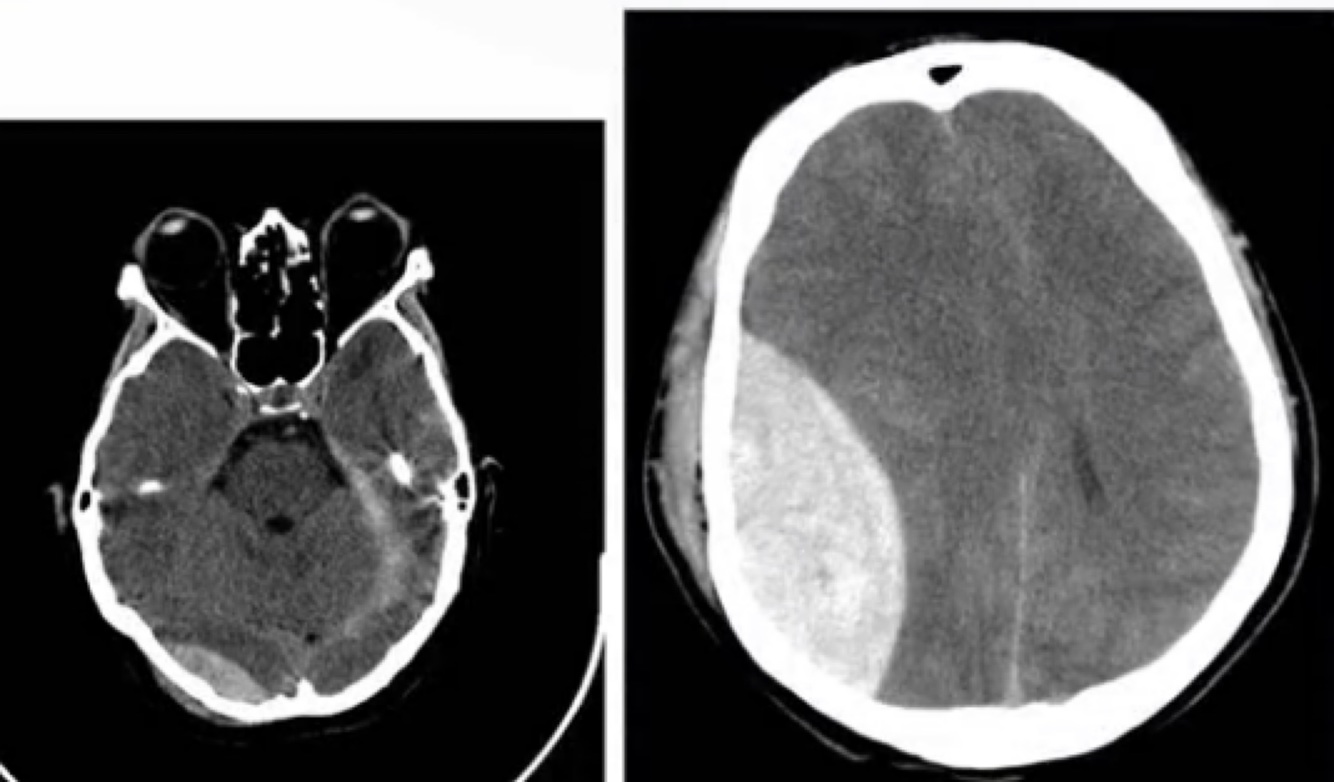

Q

Dx a seguir:

A

Hematoma epidural.

Hematoma subdural.